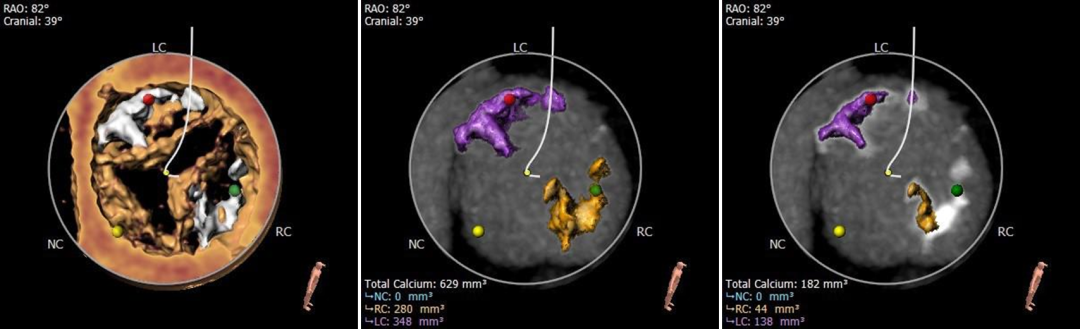

钙化分布

中度钙化,HU 600 629mm³,HU850 182mm³